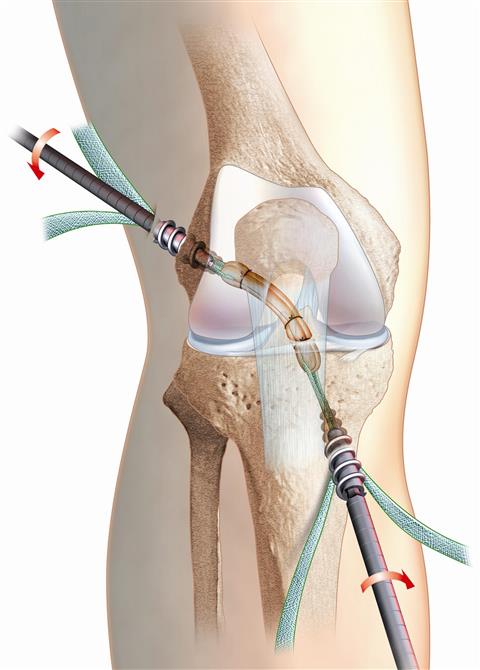

2) mise en place du greffon dans le genou sous arthroscopie.

Al'aide d'instruments de visée spéciaux, on va forer un tunnel dans le plateau tibial et un autre dans le fémur, là où précisément s'insérait le ligament croisé antérieur avant sa rupture.

La greffe est alors introduite dans l'articulation et fixée par des vis en Titane qui s'appuient dans chacun des tunnels osseux.